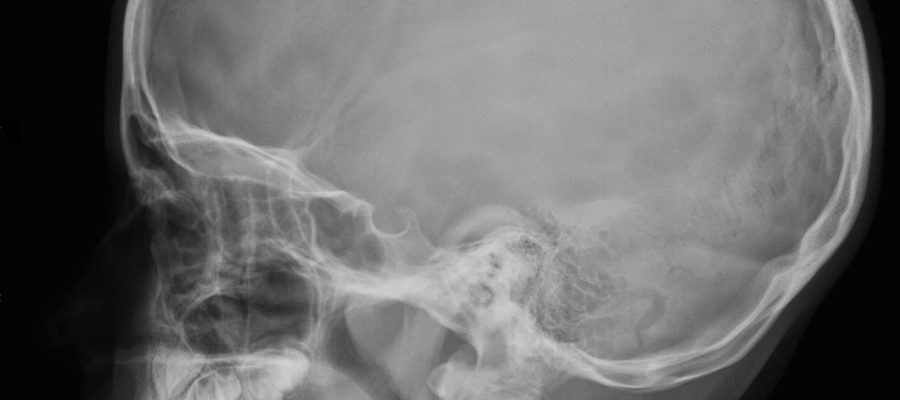

Kafatası röntgeni, baş ve boyun bölgesindeki anatomik yapıların detaylı bir şekilde incelenmesini sağlayan önemli bir medikal görüntüleme tekniğidir. Bu yazıda, kafatası röntgeninin ne olduğu, nasıl uygulandığı, hangi durumlarda gerektiği ve daha fazlası hakkında kapsamlı bir bilgi sunacağız.

Kafatası röntgeni, baş ve boyun bölgesindeki kemik yapıları, dişler ve yumuşak dokuların detaylı bir analizini sağlamak amacıyla kullanılan bir radyolojik görüntüleme tekniğidir. Bu röntgen, çeşitli medikal durumların teşhisi ve takibi için önemli bilgiler sağlar.